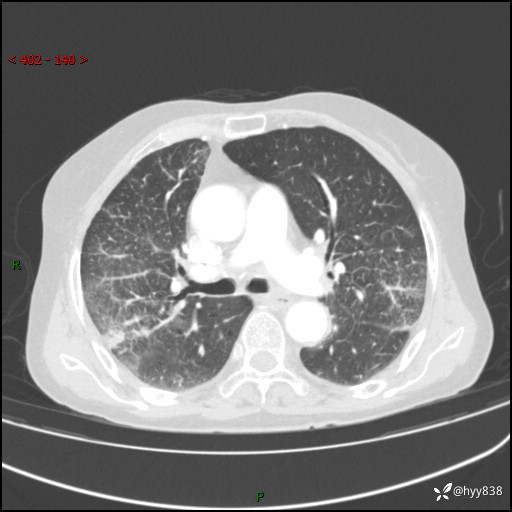

胸部CT增强(外院平扫)